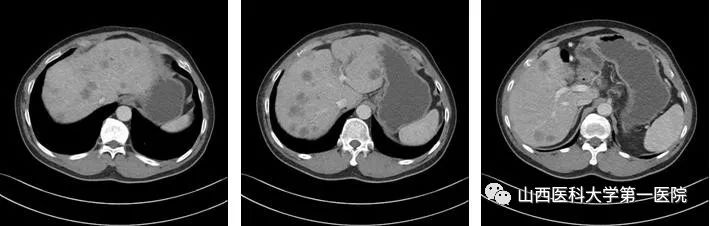

2022-01-08基线肝脏CT(静脉期)

该患者在团队成员仔细阅片、认真讨论下,因患者为PD-L1 CPS高表达人群,TMB-H基因状态,尽管目前国内外胰腺癌诊疗指南并没有对该类型患者指明个体化治疗策略,但我们通过查阅近年来已经报道的小样本临床研究以及个案报道资料,最终为患者制定了免疫联合化疗治疗策略(PD-1单抗+AG治疗6周期后,PD-1单抗+卡培他滨维持治疗),2022年8月26日,患者再次完善胸腹部CT评价疗效后,达到了大PR(部分缓解)的效果。多达20余处肝转移病灶几乎消失不见,患者可以正常工作生活。